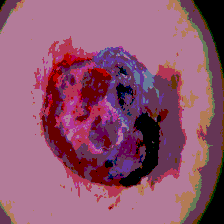

Timely identification and treatment of rapidly progressing skin cancers can significantly contribute to the preservation of patients' health and well-being. Dermoscopy, a dependable and accessible tool, plays a pivotal role in the initial stages of skin cancer detection. Consequently, the effective processing of digital dermoscopy images holds significant importance in elevating the accuracy of skin cancer diagnoses. Multilevel thresholding is a key tool in medical imaging that extracts objects within the image to facilitate its analysis. In this paper, an enhanced version of the Mud Ring Algorithm hybridized with the Whale Optimization Algorithm, named WMRA, is proposed. The proposed approach utilizes bubble-net attack and mud ring strategy to overcome stagnation in local optima and obtain optimal thresholds. The experimental results show that WMRA is powerful against a cluster of recent methods in terms of fitness, Peak Signal to Noise Ratio (PSNR), and Mean Square Error (MSE).